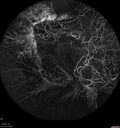

Macular ischemia left eye in type I diabetic (enlarged foveal avascular zone)213 views29 year old female with type I diabetes since age 5. Left eye has enlarged FAZ with vision of 20/20 OD and 20/60 OS. Both eyes have CSME. The left eye did have focal laserApr 12, 2023